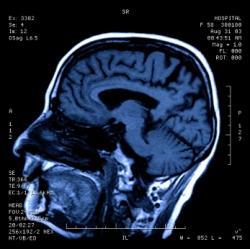

Londres, Royaume-Uni – Faire des choix peut être difficile. Mais les scientifiques viennent d'identifier la zone de notre cerveau qui les prévoie avant même qu’on ne les connaisse.

Les volontaires avaient tendance à choisir finalement la destination pour laquelle la région cérébrale du noyau caudé était la plus stimulée. Le noyau caudé, qui fait partie des ganglions de la base, est impliqué dans l’anticipation de récompenses et le mouvement volontaire. En fait, l’activité de cette région du cerveau prédit la destination qui sera éventuellement choisie parmi une sélection des préférences des individus.